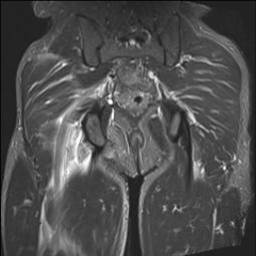

Proximal hamstring tears

Proximal hamstring tears typically occur with a violent event, such as playing sport or waterskiing. Patients will feel a tear, and there is usually a large amount of bruising, swelling and difficulty walking.

This injury can be missed. Typically an ultrasound will diagnose the proximal hamstring injury, which can be confirmed by MRI. However, as time is critical if surgical repair is considered, referral should NOT be delayed by waiting for an MRI, or the MRI should be performed on an urgent basis.